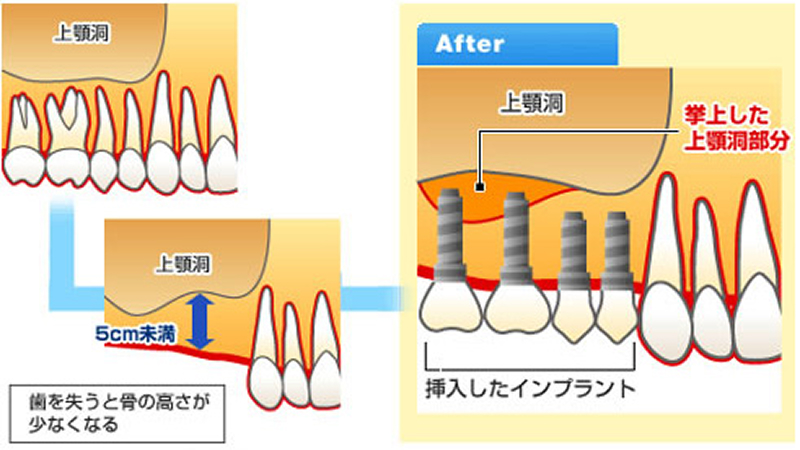

骨造成

サイナスリフト

~骨が少なくてインプラントは無理といわれた患者さんへ~

左右の上顎の、臼歯の位置の上には上顎洞(サイナス)と呼ばれる空洞が存在しています。インプラントを埋入する際、骨の厚みが十分あれば問題ありませんが、これが不足するとインプラントが骨を突き抜けて上顎洞に達してしまいます。

この問題を解決するために、上顎洞の底にある上顎洞粘膜(シュナイダー粘膜)を押し上げてそのスペースに骨を形成する処置が行われます。

- 治療期間

- 6ヶ月~1年

- 治療回数

- 手術1~2回

メリット

- 上顎の骨が薄い症例でも、インプラントに必要な骨の高さを十分に確保できます

- 広範囲に骨を造成できるため、多数歯の欠損にも対応可能です

- 手術野を直視下で処置するため、安全性が高く確実な骨造成が期待できます

デメリット

- 保険対象外となり治療費が高額になる可能性があります

- 外科的侵襲が比較的大きいため、術後の腫れや痛みが数日間続くことがあります

- 造成した骨が安定するまで、6ヶ月から1年程度の治癒期間を要します

ソケットリフト

~骨が少なくてインプラントは無理といわれた患者さんへ~

インプラントを埋入する部分(歯槽頂)から骨を造成します。骨の高さが少ない場合行います。

- 治療期間

- 約6ヶ月

- 治療回数

- 手術1~2回

メリット

- インプラント埋入と同時に骨造成を行うため、治療期間を短縮できる場合があります

- サイナスリフトに比べて外科的侵襲が少なく、術後の不快感が軽減されます

- 骨の厚みが4mm以上確保されていれば、多くの症例で適用が可能です

デメリット

- 保険対象外となり治療費が高額になる可能性があります

- 骨の厚みが極端に薄い症例は、適応外となることがあります

- 術後に一時的な腫れや痛みが生じることがあります